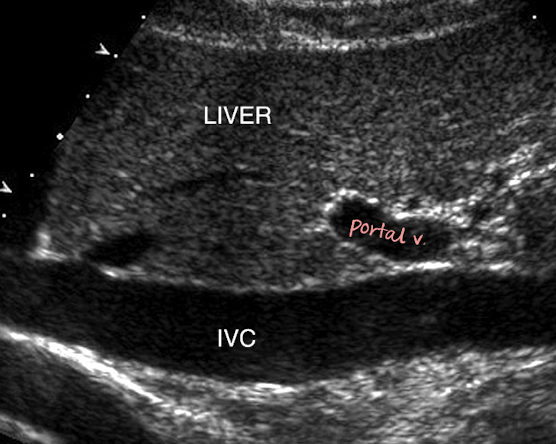

location of IVC

retroperitoneal

travels superiorly from the convergence of common iliac veins

to right of spine and AO

posterior to portal vein, intestine, liver

medial to RK

IVC info

tubular structure

collapsible with changes in respiration

many tributaries that empty deoxygenated blood into IVC